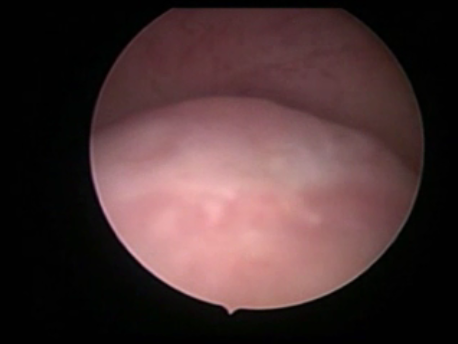

Hysteroscopy means peeping inside the uterine cavity with the help of a fine telescope varying between 2-4mm in diameter. Today a large number of surgeries can be performed via hysteroscopy due to advances in technology and instrumentation. These procedures do not involve any cut on the body and, hence, are virtually painless. The patient can be admitted on the day of the surgery and, if a laparoscopy is not needed, discharged in a few hours.

- Infertility and recurrent loss (Subfertility): Infertility means the inability to conceive and recurrent pregnancy loss means loss of 3 or more (in practice, usually 2 or more) consecutive early pregnancy (less than 5 months). Uterine pathology such as abnormal shape (septum or the T shaped uterus), submucous fibroids or polyps, and intrauterine adhesions can cause subfertility. Tubal block due to spasm or mucus plugs can contribute to infertility and can be opened by hysteroscopic cannulation.